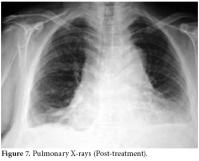

The RA disease activity score (DAS) was calculated as 6.14. Predominant findings in hand X-rays were symmetric joint erosions in carpal bones along with ankylosis leading to contracture, joint space narrowing, cystic changes, and periarticular osteoporosis (figure 5).